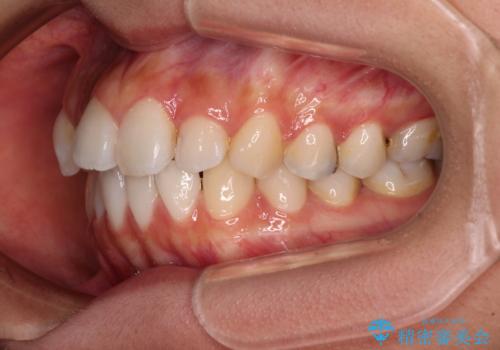

下顎の抜歯位置を左右で変えることで、最終的に上下正中をほぼ一致させることができました。

口元の突出感が認められ、更には左右で異なる咬合状態であったため、下顎右側は第二小臼歯を、左側は第一小臼歯を抜去することでバランスを取るような治療計画としました。